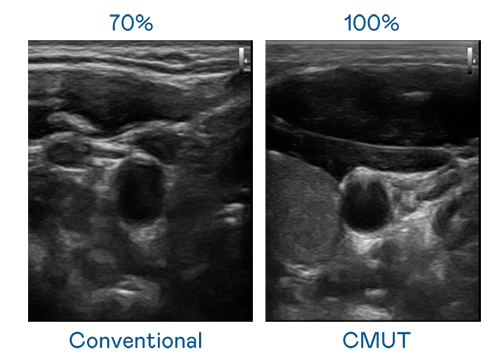

CMUT 技术是一种用电容式微机电元件来产生超音波讯号的技术。与传统 PZT 压电式技术相比,CMUT 频宽增加 30%,更宽频的超音波讯号让影像解析度大幅提升,是实现高影像品质医疗超音波扫描、促进精准医疗发展的关键技术。

大频宽带来超清晰影像

超音波影像的解析度高低,首先取决于探头能发出的讯号频宽。aa级无人二区 CMUT 可提供高清晰的超音波讯号,提供高频宽、高灵敏度、影像纹理细节更高的超音波影像,协助医护人员缩短影像判读时间及利用精准的医疗影像进行诊断。